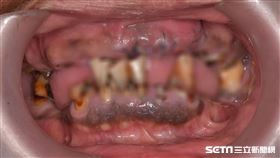

35歲民眾9成有牙周病變!醫曝「7大警訊」

一名60多歲的女性主管,因工作繁忙、三餐在外、作息不...

一名70歲阿伯,最近發現口腔中的牙菌斑明顯累積,此外...

她牙齒出了這問題 學生一見就快閃

51歲的王老師從事國小教職20多年,因罹患牙周病導致...

牙齒有這些症狀,可能是得了牙周病!

根據統計,台灣八成以上民眾患有不同程度的牙周病,許多...